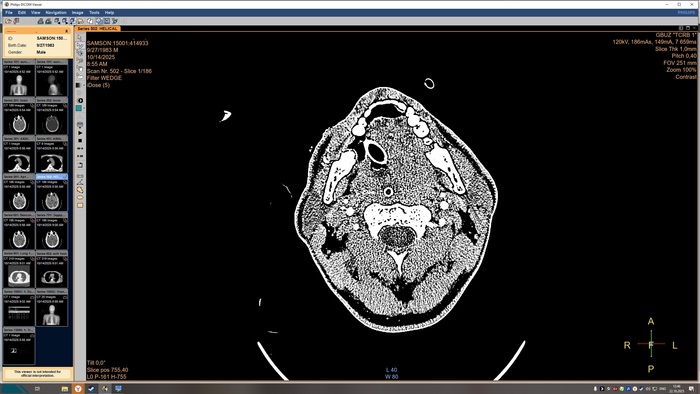

Описание КТ прикрепляю, а снимки будут в конце поста, по-другому у меня не получилось.

На топограмме, серии аксиальных срезов и реконструкций получены изображения суб- и

супратенториальных структур головного мозга от большого затылочного отверстия до крыши

черепа в нативном виде и в/в контрастированием. Определяются: справа четко

идентифицируемые внутричерепные интрапаренхиматозные гиперденсные неоднородные

очаги, копящее контрастное вещество, плотностью до 51-55ед.Х., размером: в проекции

лучистого венца 8х8х9 мм, в проекции продолговатого мозга 21х26х19 мм, Срединные

структуры мозга не смещены. Боковые желудочки: правый до 10,2 мм, левый до 12,9 мм,

третий-2,6 мм, четвёртый-13,8 мм. Селлярная и хиазмальная области без видимых

патологических изменений. Цистерны основания мозга, конвекситальные ликворные

пространства и борозды полушарий большого мозга сужены. Оболочки мозга без

особенностей. Миндалины мозжечка расположены соответственно возрасту. Дополнительных

образований и жидкостных скоплений в воздухоносных полостях височных костей с обеих

сторон, полости носа и его придаточных пазух не выявлено. Содержимое глазниц

визуализируется без особенностей. Признаков остеолитического, -пластического процессов,

аномалий развития и/или травматических повреждений костей черепа исследованного уровня

Заключение

КТ-признаки очаговых образований головного мозга. КТ-признаки правосторонней

верхнедолевой сегментарной б/пневмонии. ДИ ГОП.

Снимки КТ